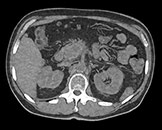

Выполните просмотр требуемой области с помощью нескольких решений благодаря эксклюзивному приложению Spectral Magic Glass для вычленения данных о составе тканей.

Здесь представлена серия изображений, на которых значения воксела обозначают эффективное атомное число. Эффективное атомное число может быть дробным, обозначающим какой-либо элемент, соединение или смесь. Данное число может отличаться от порядкового номера, указанного в периодической таблице. Единица для обозначения — Z.